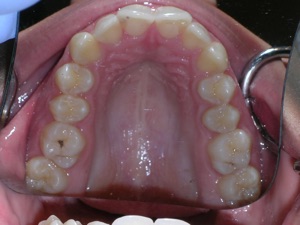

In this case, a young woman came to us with a desire to straighten her teeth. We elected to do Invisalign treatment with some enamel reduction and some dental arch expansion. Take a look...

Here she is on the day of appliance removal. You can see how the crossbite on the right has improved, as well as the lower front teeth crowding. Note that we elected to leave the lower second premolar in it’s rotated form.